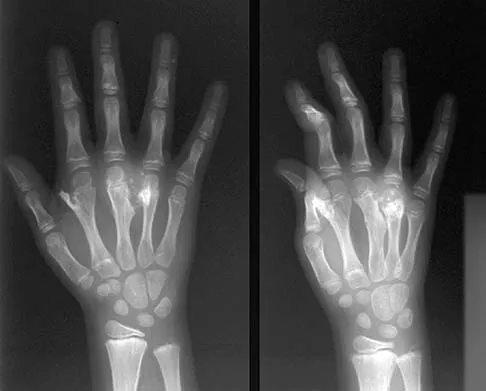

Figure 19 shows the radiograph of a 12-year-old boy who sustained an injury to his hand when another child fell on him. Management should consist of

The patient has a Salter-Harris type III fracture of the proximal phalanx of the thumb. It is usually caused by an abduction injury where the ulnar collateral ligament avulses a fragment away from the proximal epiphysis and is the most common childhood gamekeeper's injury. If there is greater than 1 mm of separation or a significant articular step-off, an open reduction, performed through an extensor aponeurosis-splitting approach, is required to reestablish joint congruity and stability. Percutaneous or closed methods of reduction are usually ineffective. The dorsal approach avoids the volar neurovascular structures. Since the ulnar collateral ligament is still attached, this area does not need to be visualized. The major goal is to reestablish joint congruity and bony stability. This can be easily performed via the dorsal approach. Carey TP: Fracture and dislocations of the phalanges, in Letts RM (ed): Management of Pediatric Fractures. New York, NY, Churchill Livingstone, 1994, pp 435-436.